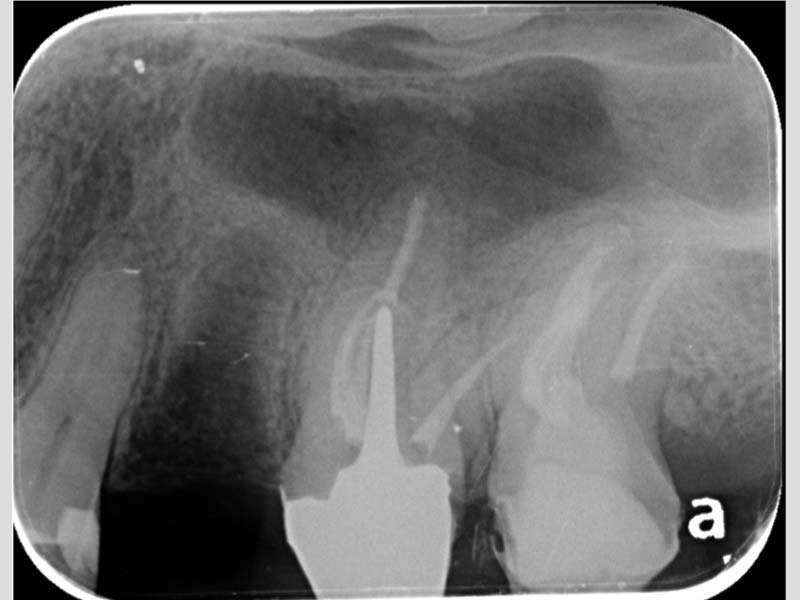

治療前X光:診斷左上顎最後三尺為均需要根管治療

左上顎第二小臼齒:顯微鏡下確診牙裂,建議拔除

左上顎第一大臼齒:為五根管的難症(罕見變異多根根管)

左上顎第二大臼齒:也是五根管的難症(罕見變異多根根管)

治療後X光